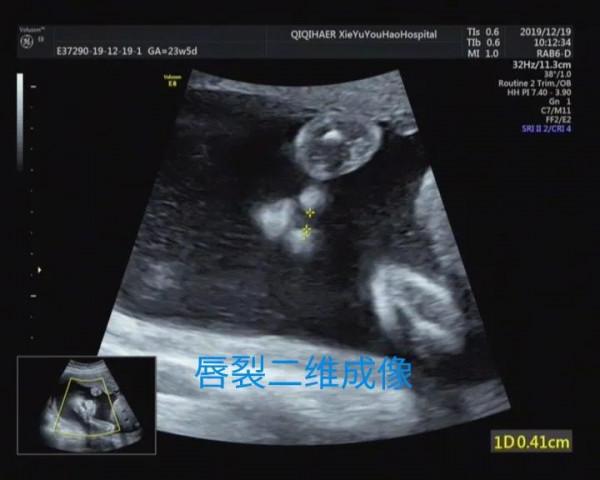

寶媽們比較關心二維超聲與三維超聲有什麼區別,簡單的科普解釋,超聲醫生診斷畸形是透過多切面,動態二維超聲判斷的,三維成像只起到必要時的輔助作用。胎兒表面結構的三維影象,客觀逼真,一旦存在胎兒體表的畸形,如唇裂、腦膨出、脊柱裂、臍膨出、腹裂、肢體或手腳畸形,三維成像能夠讓孕婦及家屬一目瞭然,讓產科醫生或兒科醫生更能結合實際情況提供諮詢建議,方便選擇下一步的處理方案。下面分享幾個小病例,讀者可以自己體會。

病例1

比如病例1,5兒外科醫生及寶媽們均可以直觀看到異常,醫生會解釋的相對輕鬆,寶媽及家屬參照直觀三維成像理解的也能更透徹,更相對安心。